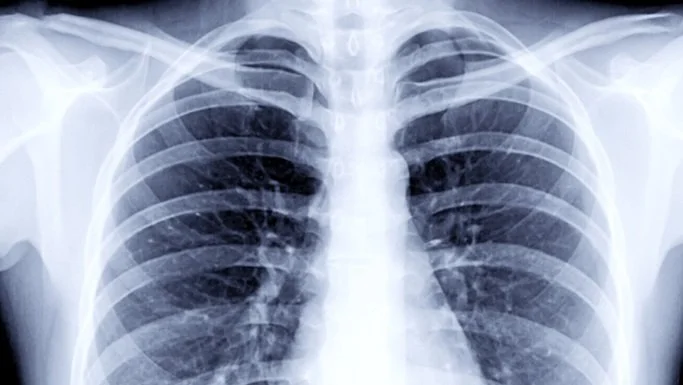

The MIDRC is responding to an unmet need of the medical imaging community as doctors and scientists seek to better understand SARS-CoV-2, the virus that causes coronavirus disease 2019, or COVID-19, and its effects on the human body. By collecting and integrating images and their data via a dynamic, secure networked system, the MIDRC will provide a large-scale, open, common framework to enable technological advancements, guide researchers’ validation and use of AI (artificial intelligence), and translate clinical systems for the best patient management decisions.”